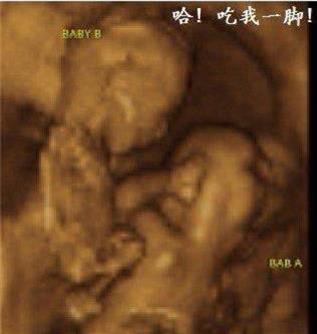

擁有雙胞胎寶寶父母當然都很幸福,雖然養育兒女付出了雙份的辛苦,但同時也收穫了雙份的歡樂。  他們在媽媽肚子的時候就已經頻頻互動,有時候還會親吻,打架!超級萌,超級感人!

雙胞胎居然在打架   其實雙胞胎是心有靈犀的,看下面的這兩對雙胞胎,你就知道有多羨慕了 1、當這對雙胞胎從媽媽肚子裡生出來的那一刻,竟讓醫院所有人都震驚了!!原來這對雙胞胎竟是.手拉手出生的! 而當寶寶生下來的一刻,大家都驚呆了  爸爸都感動的哭啦 2、雙胞胎中的弟弟出生就沒呼吸,哥哥給他加油打氣,居然拉起弟弟的手 出生時,弟弟被查出了胸部感染,需要靜脈注射抗生素,這時哥哥竟然把手伸過來緊緊握住了弟弟的手。 「不要怕,哥哥保護你。」  就在護士向媽媽解釋如何治療的時候,突然哥哥伸出手去摸瓊斯,弟弟感覺到了就伸手來回應,然後他倆的手緊緊的握在了一起。這一幕太令人難以置信了!